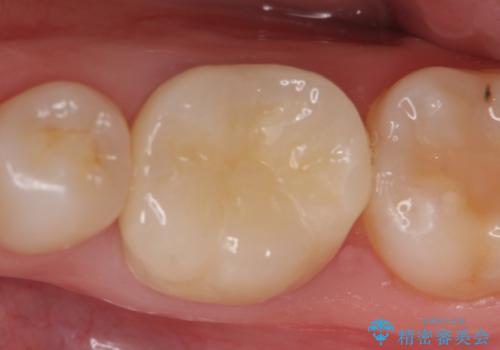

40代女性 保険の銀歯の総入れ替え

左上6番の歯のみ、根管治療からのやり直しが必要でしたが、他の歯は「金属の除去→内面の徹底的な清掃と形態修正→セラミックの製作」という単純な操作のため、基本的には短期間で治療を終えられることが多いです。